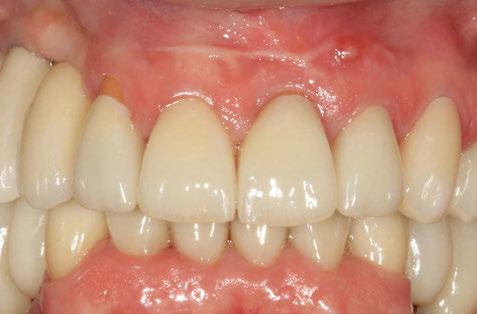

E-max CAD sobre implante

E-max CAD sobre diente natural

El innovador Disilicato de Litio (LS2) del sistema de cerámica vítrea IPS e.max CAD no solo ofece una altísima estética sino que también es de 2,5 a 3 veces más resistente 360 MPa que el resto de cerámicas de vidrio. Por ello, este material cubre todos los requerimientos estéticos y también representa una alternativa eficiente a las restauraciones unitarias de Zr02 (Zirconio).

El innovador Disilicato de Litio (LS2) del sistema de cerámica vítrea IPS e.max CAD no solo ofrece una altísima estética sino que también es de 2,5 a 3 veces más resistente 360 MPa que el resto de cerámicas de vidrio. Por ello, este material cubre todos los requerimientos estéticos y también representa una alternativa eficiente a las restauraciones unitarias de ZrO2. (Zirconio)

IPS e.max está avalado por la experiencia clínica que ha demostrado durante años, tanto en estética como en resistencia. La amplitud de elección del material, según el caso, en conjunción con la técnica empleada en nuestro laboratorio dotarán a los trabajos de la mayor estética para sus pacientes.